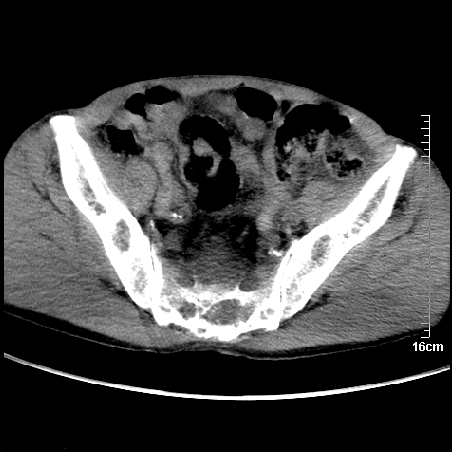

1、骶尾部巨大软组织肿块,部分骶尾骨以被软组织肿块代替,呈不规则侵蚀;病变突向盆腔内;增强扫描病变呈不均质强化;首先考虑脊索瘤。不支持的一点就是病变内无钙化。

部分骶尾骨已被软组织密度的肿瘤所取代,同意“首先考虑脊索瘤,不除外转移瘤”的意见。

首先考虑脊索瘤,不除外转移瘤。